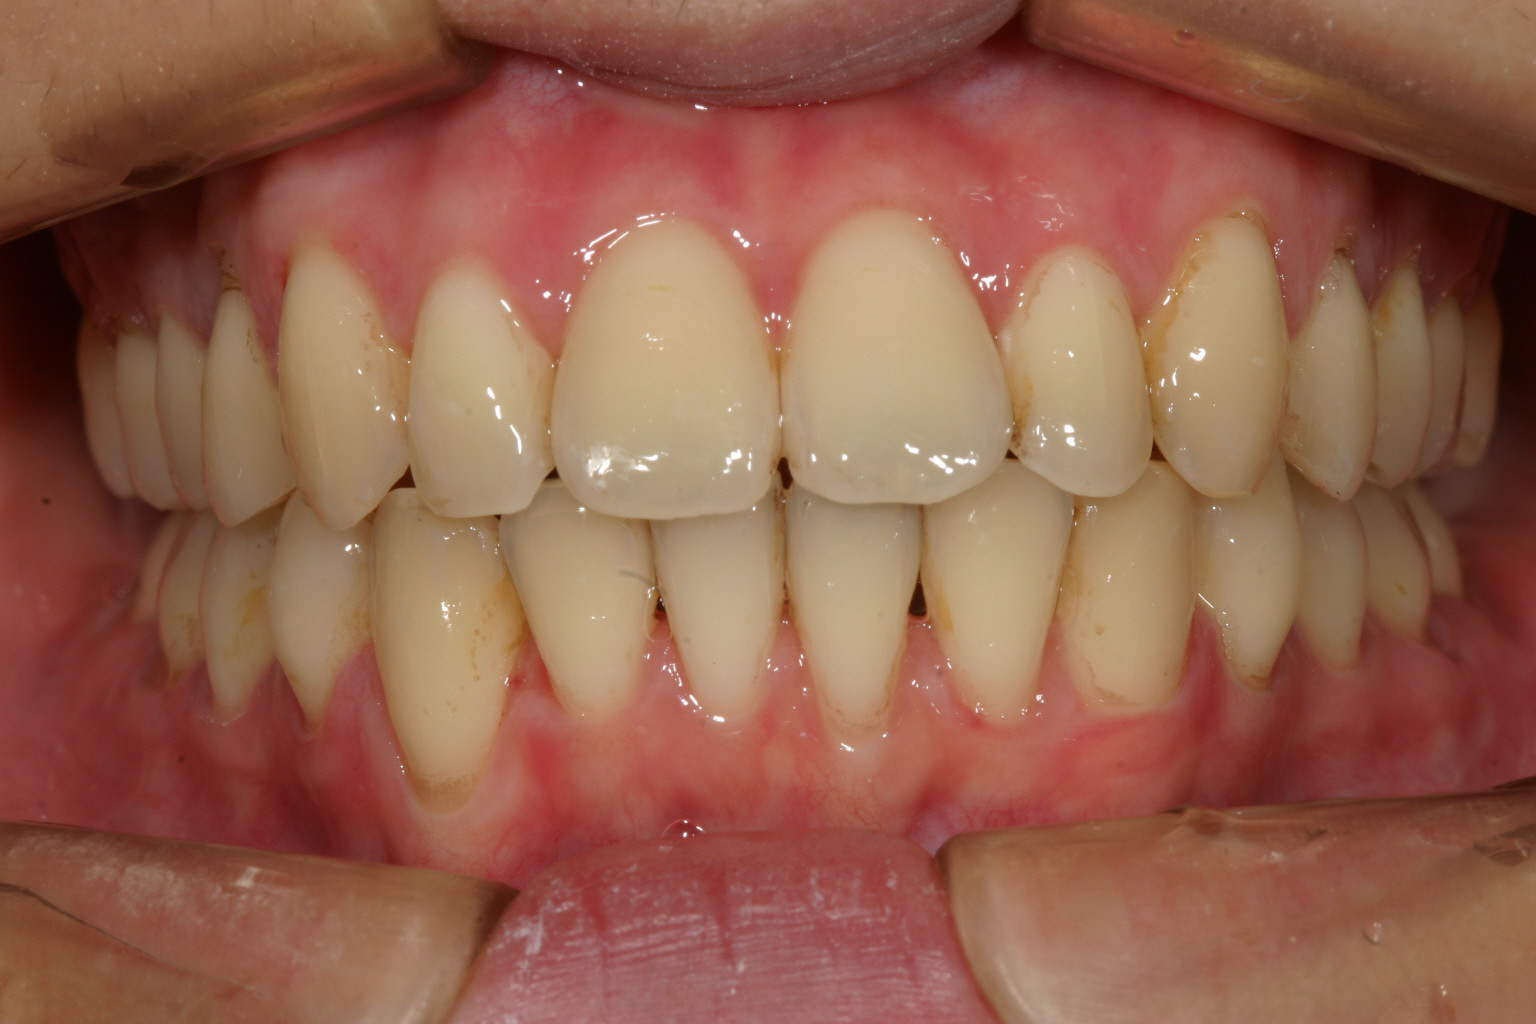

綺麗なアーチに改善いたしました。

出っ歯観も問題ありません。